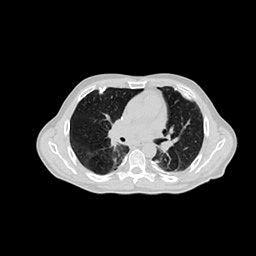

4.4 Limited-Angle CT Reconstruction

To test the proposed framework’s performance on limited-angle reconstruction, we redo the experiment in the above section with the angular range changing from to for parallel-beam geometry and to for fan-beam geometry, one projection per degree. The experiment results are shown in Fig.6. Also, the ground truth and the limited-angle CT reconstruction results of different methods are shown in the row of Fig.7 (parallel-beam, LIDC-IDRI dataset), and Fig.8 (fan-beam, LIDC-IDRI dataset).

(a) Ground Truth

30.15dB

(b) ASD-POCS

39.35dB

(c) RBP-DIP

27.10dB

(d) DIP

23.88dB

(e) MED50

20.59dB

(f) RED-CNN